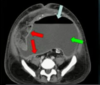

***_PRESENÇA DE ABSCESSO ENTRE SIGMÓIDE E BEXIGA DO PACIENTE._*** ***_COMPLICAÇÃO DA DIVERTICULITE COM O ABSCESSO._*** ***_NESSE CASOS = DRENAGEM + ANTIBIOTICOTERAPIA._*** ***_SIGMOIDECTOMIA APÓS 6 MESES._***